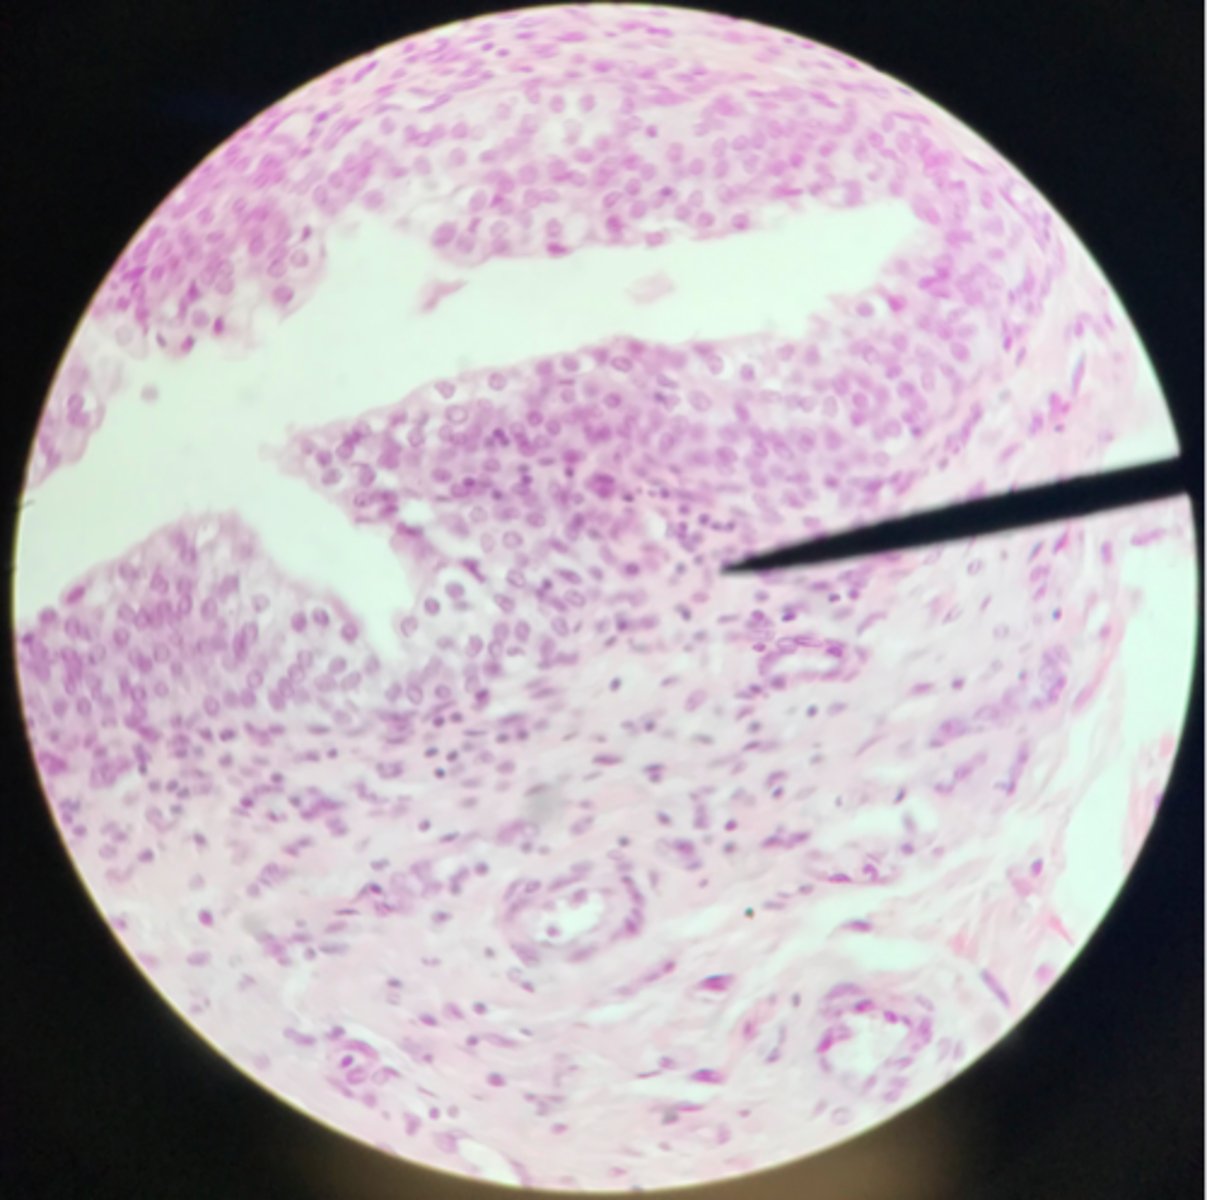

Transitional epithelium of the bladder

What tissue is depicted on the slide above the pointer?

Basement membrane

What cells of transitional epithelium are located where the pointer is at?

Ureter

Transitional epithelium

What structure/organ is depicted on this microscope slide?

What tissue makes up a majority of it?

Transitional epithelium

What type of tissue makes up the inner lining of the ureter?

Urinary bladder

Transitional epithelium

What organ is depicted on the slide? What type of tissue is the main component?

Ureter

Note the smooth muscle layer surrounding the transitional epithelium

What organ is depicted on this slide?